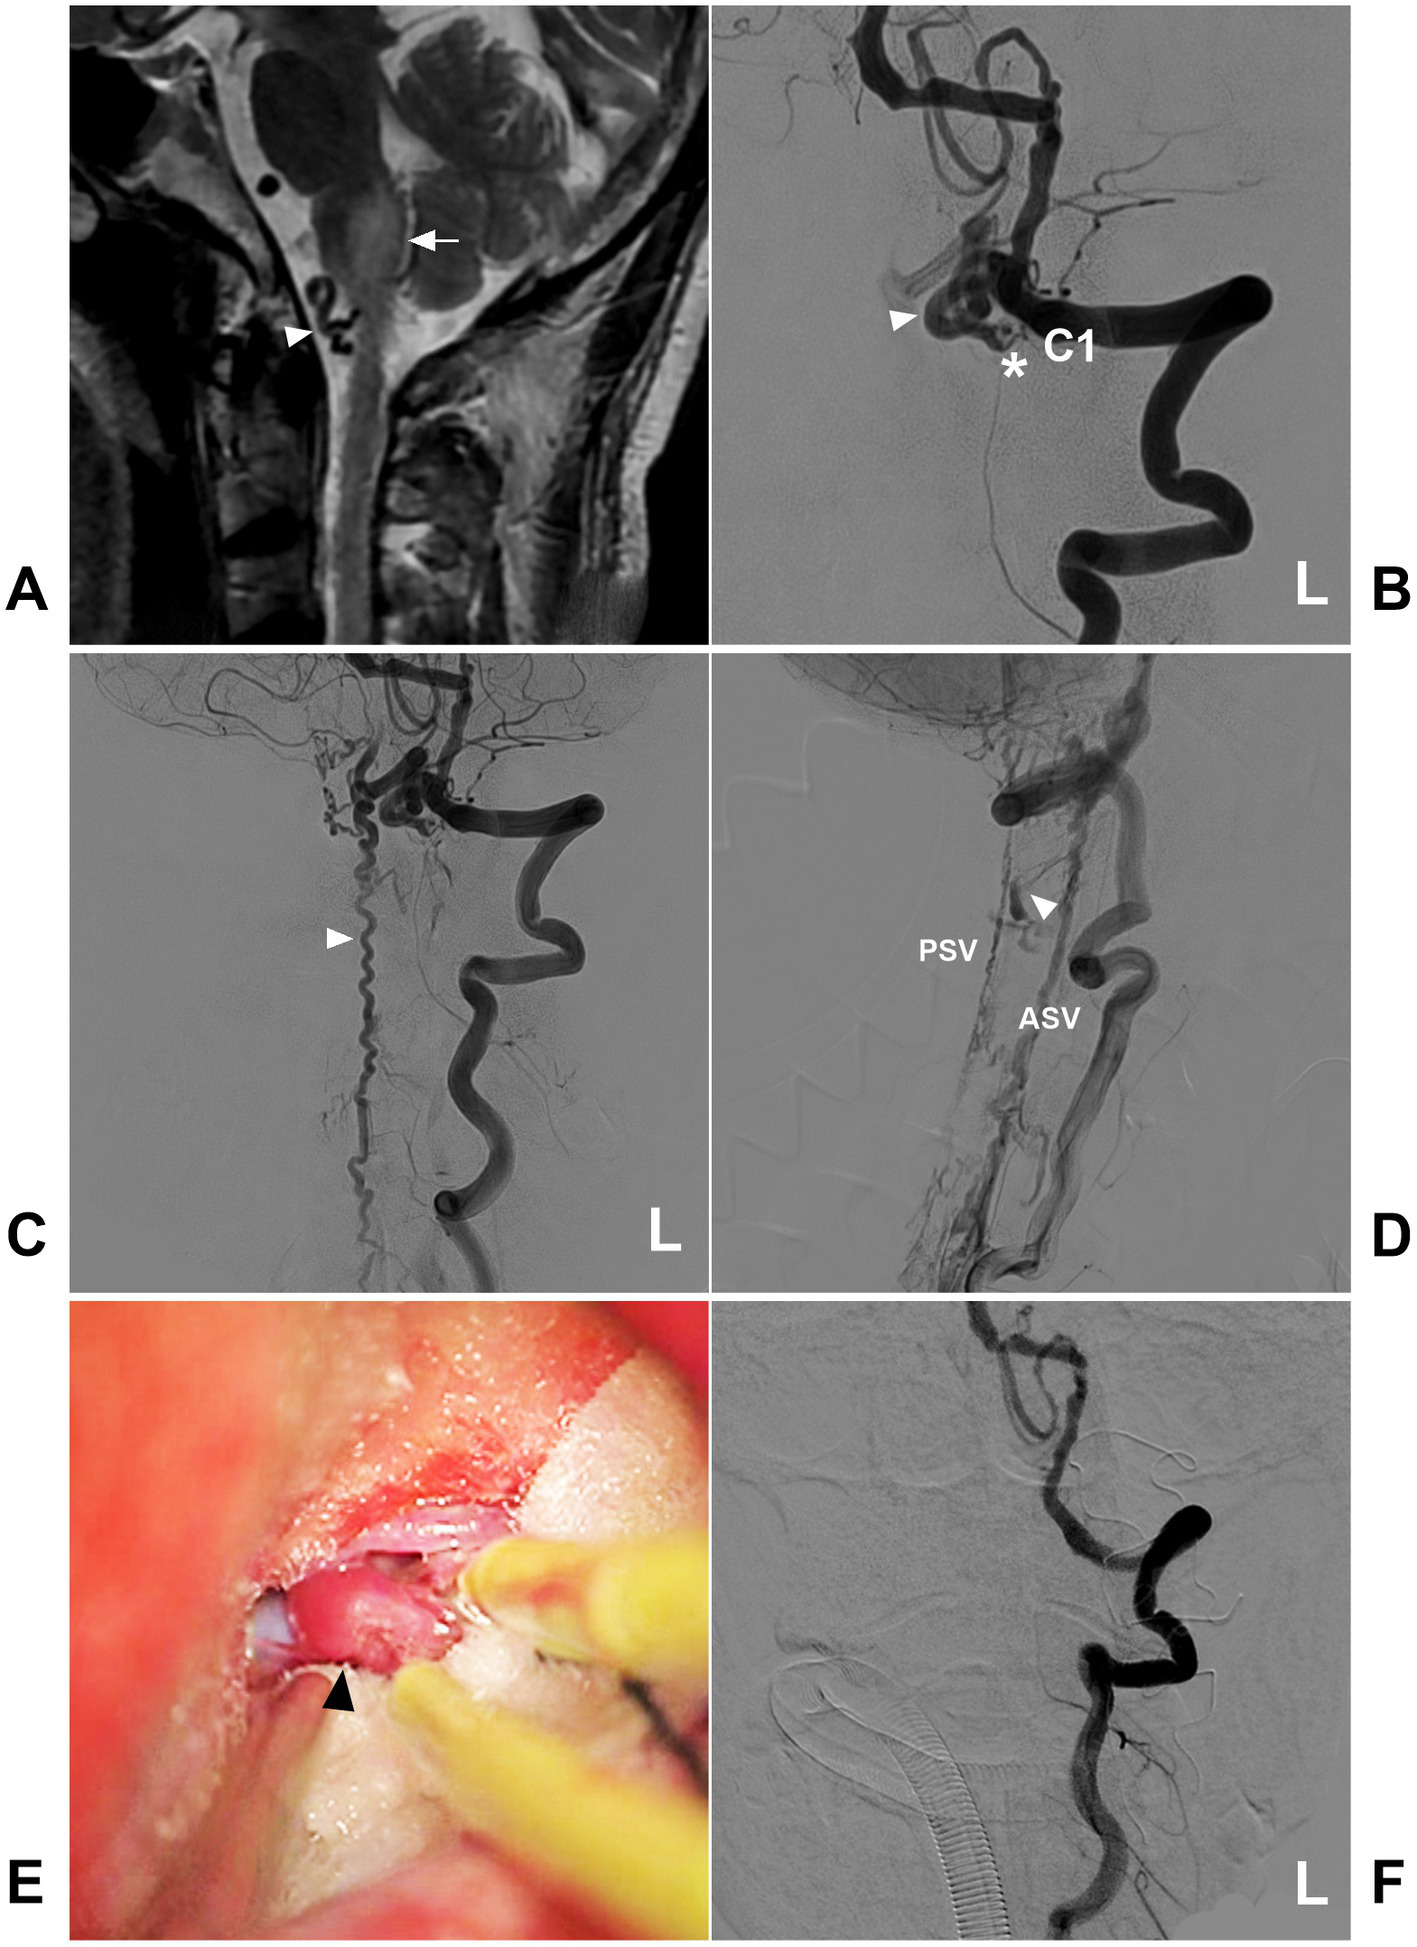

Figure 8

Open surgery in a high cervical CCJ DAVF with downward drainage. (A) MRI showing edema (arrow) of the medulla oblongata and abnormal vessels (arrowhead) in the front of the brainstem. (B) Arterial phase DSA of the left VA showing a CCJ DAVF (asterisk) fed by the C1 radicular artery. The drainage went into the intracranial vein (arrowhead). (C) Late arterial phase DSA of the anterior posterior view showing downward drainage into the perimedullary vein (arrowhead). (D) Late arterial phase DSA of the lateral view showing downward drainage, including downward ASV and PSV, and lateral drainage by the bridging and radicular veins (arrowhead). (E) Intraoperative image showing the thick arterialized draining vein (arrowhead). (F) Postoperative DSA showing that the DAVF was obliterated after the draining vein was coagulated and cut. ASV, anterior spinal vein; C1, first cervical vertebra; CCJ, craniocervical junction; DAVF, dural arteriovenous fistula; DSA, digital subtraction angiography; L, left; MRI, magnetic resonance imaging; PSV, posterior spinal vein; VA, vertebral artery.